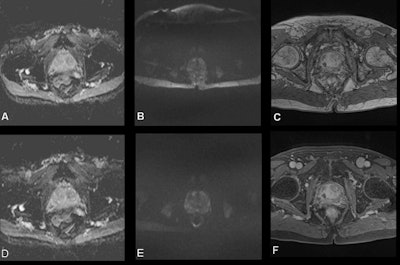

A total of 20 out of 23 MRI protocols, consisting of 111 sequences, were optimized by modifying their sequence parameters. Preoptimization, only 15% of the T2-weighted images were nondiagnostic, whereas 40% of apparent diffusion coefficient (ADC) maps, 50% of high b-value diffusion-weighted images, and 41% of dynamic contrast-enhanced scans were considered nondiagnostic.

After applying the standardization process across the several prostate MRI protocols, the majority of the scores were increased, resulting in 80% of ADC maps, 74% of high b-value diffusion-weighted images, and 88% of dynamic contrast-enhanced MRI to be partially or fully diagnostic.